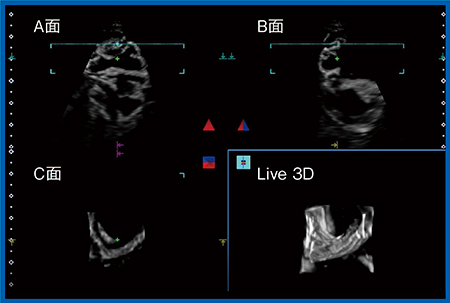

通常の超音波検査では,1つのスライス面しか画像化できず,近くで同時に起こっている現象でもスライス面以外は観察できない。それを可能にするために開発されたのがマトリックスプローブ(PSI-40VX)である。マトリックスプローブでは,スライスの厚さ方向を含めたボリュームデータ(3D)の収集が可能で,これに時間を加えた“4D Imaging(Live 3D Image)”によって,ほかのモダリティとは異なる,時間的にズレのない真の3D画像の観察が可能となる。

図2は82歳,女性で,腸閉塞の下腹部創部直下の癒着症例である。腸閉塞の診断で問題になるのが腸管のバイアビリティであり,特に非閉塞性腸管虚血(NOMI)は腸管の虚血の診断が難しいが,4D Imagingで腸管の広範囲のデータを取ることでバイアビリティの評価が可能になることが期待される。

図2 マトリックスプローブを用いた造影による腸管のバイアビリティ評価